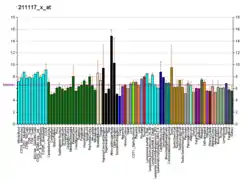

Tissue distribution

ERβ is expressed by many tissues including the uterus,[23] blood monocytes and tissue macrophages, colonic and pulmonary epithelial cells and in prostatic epithelium and in malignant counterparts of these tissues. Also, ERβ is found throughout the brain at different concentrations in different neuron clusters.[24][25] ERβ is also highly expressed in normal breast epithelium, although its expression declines with cancer progression.[26] ERβ is expressed in all subtypes of breast cancer.[27] Controversy regarding ERβ protein expression has hindered study of ERβ, but highly sensitive monoclonal antibodies have been produced and well-validated to address these issues.[28]